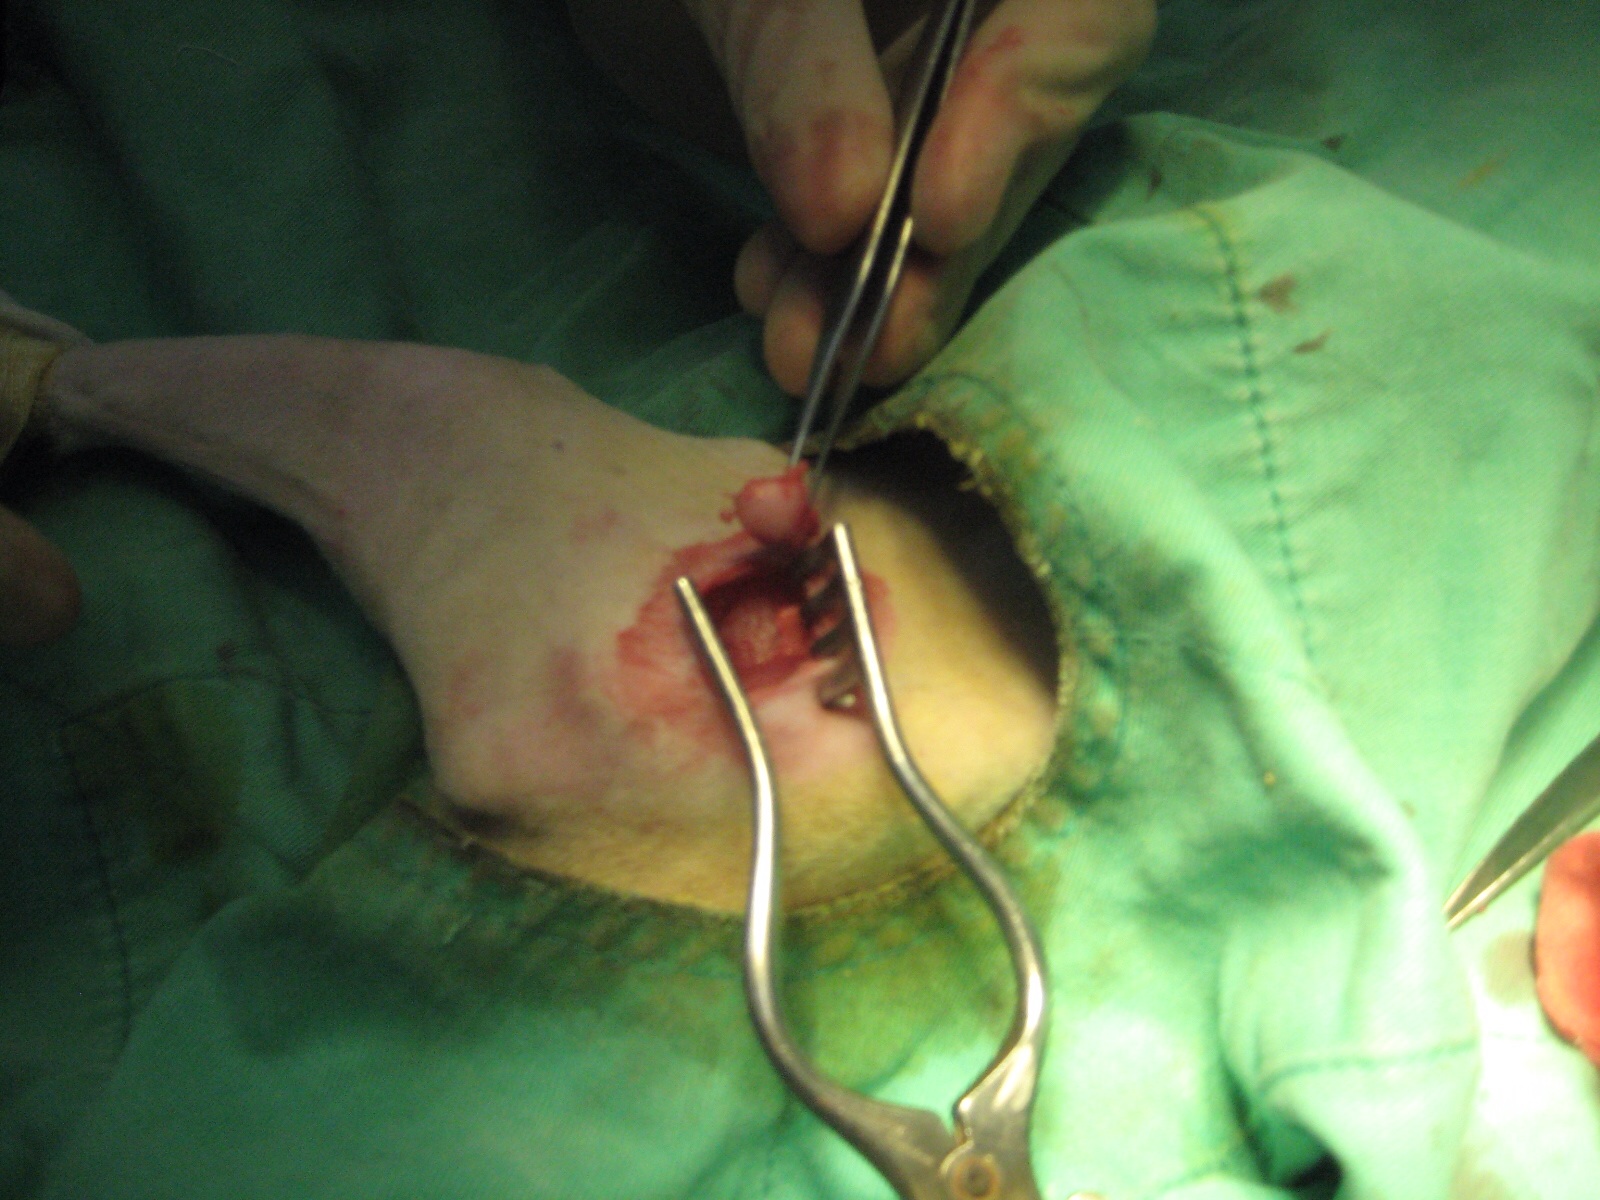

- 編號: 3949

主題: 高雄小貓被機車撞到骨折 申請者姓名: Sexson Dai 花色: 申請日期: 2014-02-09 12:00:12 申請者部落格: 申請者臉書網址: 所在縣市/合作醫院: 高雄市/新德民動物醫院 治療費用: 13550元 需求人數: 15人 已結案 (2014-03-24 18:14:14) 報名人員: 彭小花(已付款)、Patrick x2(已付款)、Kristy Lee(已付款)、Eva Tsai、烙跑專用(已付款)、徐米奇(已付款)、Melody Wu(已付款)、julie lee(已付款)、橙小瑩(已付款)、Hsiao-Peng Su(已付款)、孟孟 x2(已付款)、Meng-Chen Tseng(已付款)、小娃(已付款)、佳淳(已付款)、 候補人員: Bagel Li、 動物病情說明: 貓咪在本月大年初三和志工朋友去吃早餐遇到的,走路非常異常是用蹬的,詢問早餐店老闆說一個星期前被機車撞到,前腳有明顯外傷,指甲已外翻,後腳雖無明顯外傷但後腳無力,無法正常行走和跳,當下就和另一名志工朋友就請老闆幫我們留意,準備誘補小貓,小貓已確定是浪貓,因為貓媽媽會帶他們來向早餐店老闆討食,我於今天民國103年2月4日下午三點左右送到高雄德民動物醫院,醫生初步診斷左後腳有照X光確定斷掉,右前腳掌指甲外翻,手術費及醫療費醫生估約10000左右 動物近況說明: 小貓術後身體狀況正常,恢復的不錯,我會將他帶回家中途療養,直到好了,在將小雪找個好主人